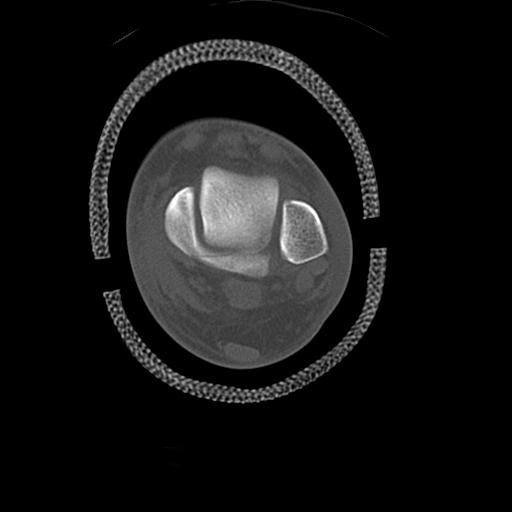

49554 3/13 膝 4R 3/16 4R 1/18 2R 78歳男性 膝蓋骨骨折

102755 1/4 2R 1/15 2R 右足関節 68歳女性 右三果脱臼骨折